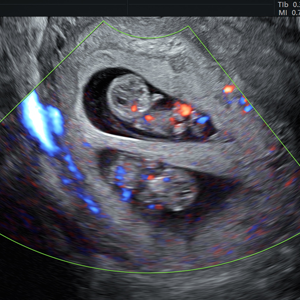

- Pionero en México en ofrecer diagnóstico por ultrasonido dentro del consultorio, así como en incorporar tecnología 3D y Doppler.